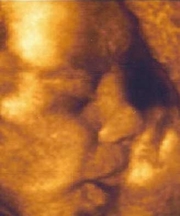

uzi_3dНекоторые молодые мамы по примеру своих подруг или под впечатлением телевизионной передачи про новинки в методах исследования плода мчатся в ближайшую больницу, чтобы испытать эти самые новинки на себе.

Безусловно, на протяжении долгих девяти месяцев очень хочется рассмотреть своего малыша как можно лучше. Интересно узнать, какие у ребенка черты лица, как он зажмуривает глазки, зевает, улыбается или даже сосет пальчик. Обыкновенное черно-белое 2D УЗИ не обладает такими возможностями.

Поэтому новое ультразвуковое исследование в трехмерном изображении становится все более и более популярным. Самый простой аппарат УЗИ показывает точечную картинку, в которой разберется только опытный специалист. Изображение 3D значительно интереснее - оно цветное и объемное.